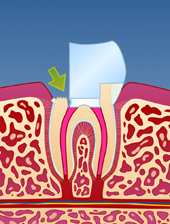

En rotfylt tann er ofte svekket på grunn av store fyllinger og lite gjenværende tannsubstans (fig. I). Som resultat vil en rotfylt tann være mer utsatt for å knekke enn en tann som ikke er rotfylt (fig. II-III). Dersom rotfyllingen blir utsatt for lekkasje over lengre tid, kan bakterier komme til og lage en ny infeksjon i den rotfylte tannen (fig. IV). Der er derfor viktig å kontakte tannlege snarest dersom deler av en rotfylt tann knekker av.

| figur I | | figur II | | figur III | | figur IV |